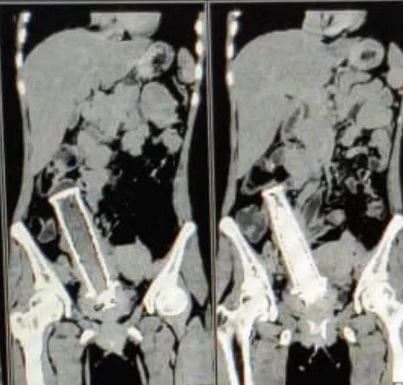

Αυτές λοιπόν, σύμφωνα με το Cover Asia Press, έδειξαν πως όλα ήταν αποτέλεσμα της ύπαρξης μίας χειρολαβής από μηχανάκι στην μήτρα της!

Το συγκεκριμένο αντικείμενο ήταν μέσα της για περίπου δύο χρόνια, με αποτέλεσμα να δημιουργήσει μολύνσεις.

Η μήτρα της είχε διαβρωθεί τελείως και για αυτό έπρεπε να την αφαιρέσουμε, επισκευάζοντας παράλληλα την ουροδόχο κύστη μέσω ενός στεντ».